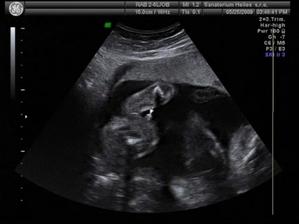

19.2.2009 - KO u Dr. Čeká nás další UTZ a odběry.